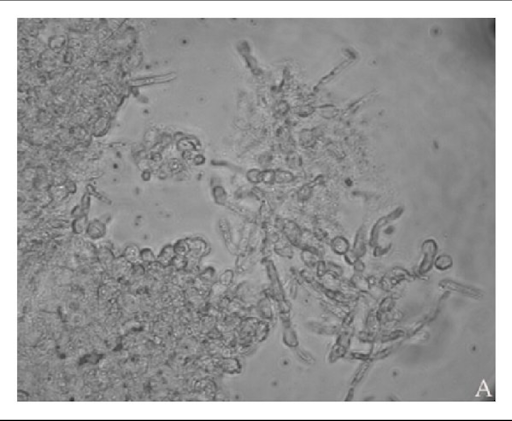

FUNGAL HYPHAE ( Thread Like Structure )

Under the microscope, the doctor looks for:

Fungal hyphae (thread-like structures)

Yeast cells or budding yeast

Spores

A positive KOH test means fungal elements are seen.

A negative test means no fungus is detected.